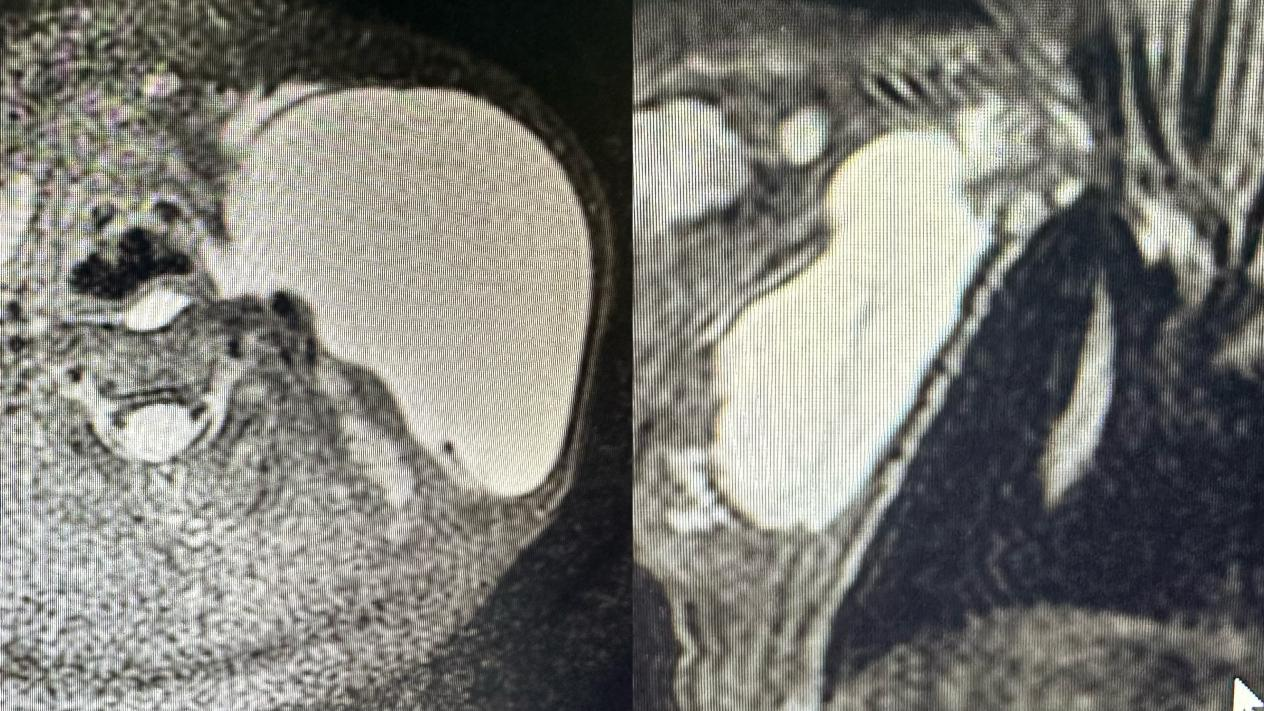

胎儿淋巴管畸形磁共振检查

儿童淋巴管畸形磁共振检查

【辅助检查】1、超声检查提示无回声区,有分隔,呈囊状改变,CDFI:无血流信号,2、磁共振检查提示长T1长T2信号,囊状改变,压脂序列呈高信号,增强无明显强化。目的:1、超声检查用于明确诊断,2,磁共振检查用于了解淋巴管畸形病灶范围、侵及周围组织情况以及是否包绕重要器官如血管神经以及气管等。